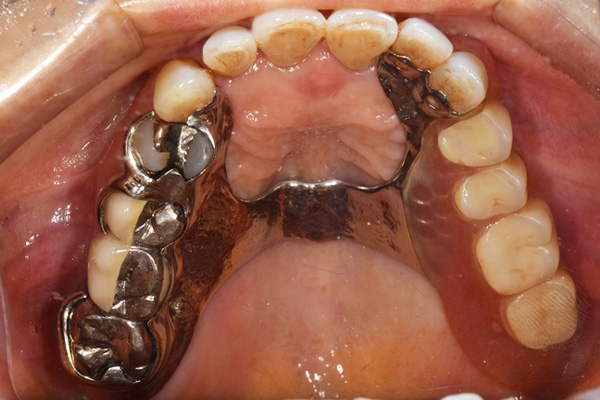

ケース3(インプラントを用いた部分入れ歯)

右上と左下の歯がない方です。 上の入れ歯の安定が悪く、作り直したいとのことでいらっしゃいました。 今お使いの上の入れ歯を見てみると、口蓋部分が抜けており、安定性に欠ける構造になっていました。この入れ歯はノンメタルクラスプデンチャーといって、金属のバネを使用しない 入れ歯になります。これは見た目は良いのですが、歯への負担が大きいことと、入れ歯自体がやわらかいため、噛むには不便なことがあります。

入れ歯は極力薄くするために金属を使用しました。しっかり噛める様にするため、ノンメタルクラスプデンチャーにはしませんでした。

上の入れ歯(表)

上の入れ歯(裏)

下の入れ歯

入れ歯を入れた状態のお口の中の写真です。バネも極力目立たないように作成しています。

年齢 70代・女性

主訴 上の入れ歯の安定が悪く、作り直したい

治療期間 5ヶ月

治療費 .診査診断:55,000円

.インプラント埋入:165,000円

.アバットメント:33,000円

.義歯:330,000円

治療方針 右片側のみ奥歯がない方です。

この様な場合入れ歯は反対側に維持を求めるため、大きな入れ歯になりがちです。

そのため違和感が強いことがおおいです。

また、片側だけないですので、安定もむずかしくなります。

そこで、安定をよくするために、右の奥歯の位置にインプラントをいれて、義歯が揺れない様にすることにしました。

治療内容 レントゲンをみて最低限の長さのインプラントを右上の奥歯の位置に埋入しました。インプラントと骨の結合(オッセオインテグレーション)と歯肉の治癒を待ち、アバットメントをいれて型取りをして、入れ歯を作成しました。極力薄くするために、金属をもちいた入れ歯にしました。

特記事項 インプラントは必ず成功するというものではありません。 また治癒も人それぞれで、長くかかることもあります。 入れ歯を入れ終わったあとも、アバットメントが緩んできたり、入れ歯が歯ぐきにあたって痛いところもでてきますので、調整は必要になります。